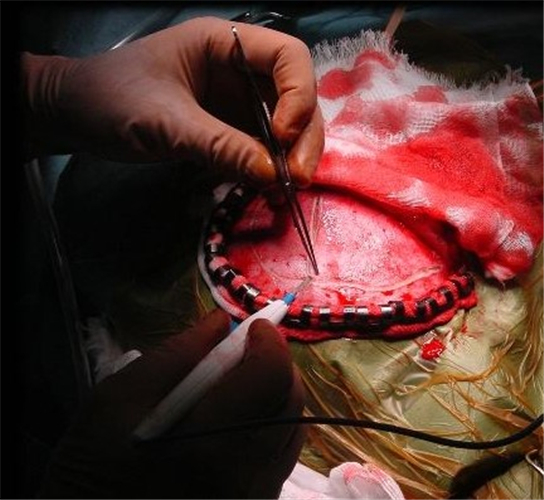

手術治療煙霧病引起的腦血管痙攣

手術治療腦血管痙攣

手術治療腦血管痙攣的

手術治療腦血管痙攣合併動脈瘤

腦血管痙攣手術中